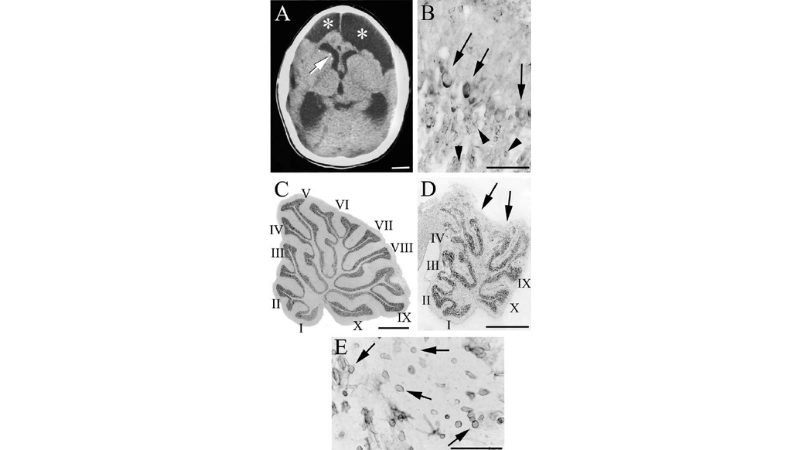

A microscopic view of the LCM virus shows its rodent-transmitted viral particles, highlighting the source and mode of human infection. The virus primarily targets the nervous system, causing inflammation and fever.

Learn how congenital LCM impacts newborn brain development

LCMV may lead to hydrocephalus in severe infections